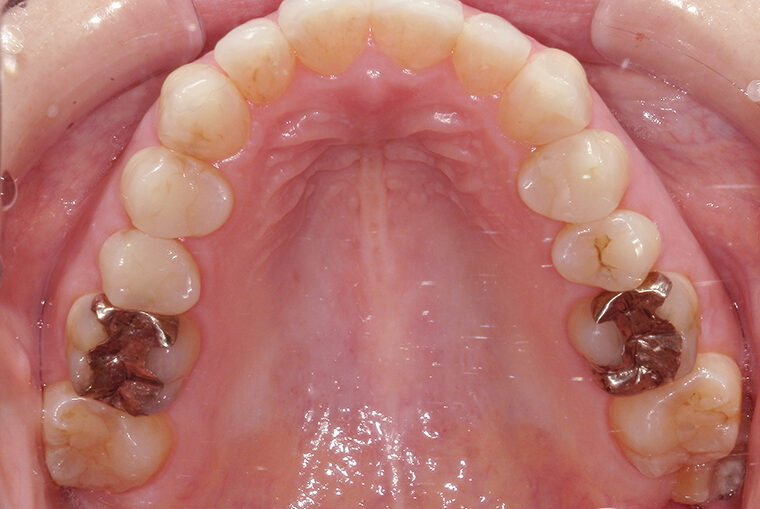

Case Study39歳女性ガタガタな歯のマウスピース矯正-矯正期間9ヶ月